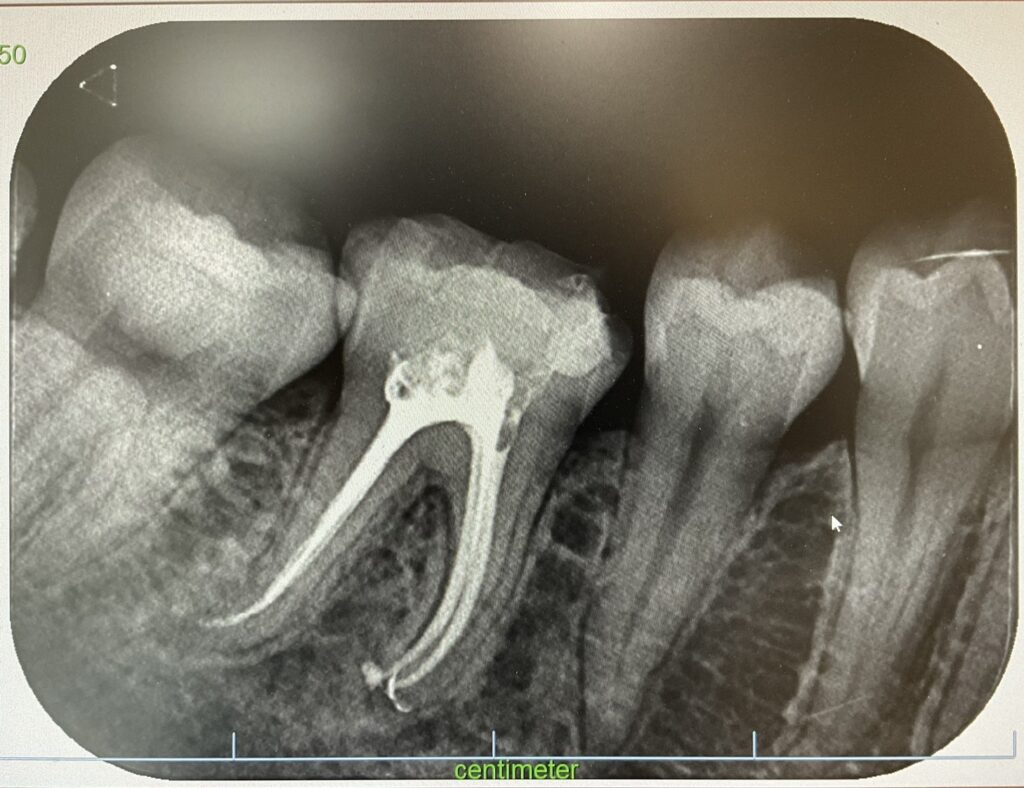

抜随はWave One Gold, 感染根管治療処置はK3システムとハイテク器具を導入し使用しております。

Wave one gold で抜随後、垂直加圧根管充填を行なったデンタルX線像